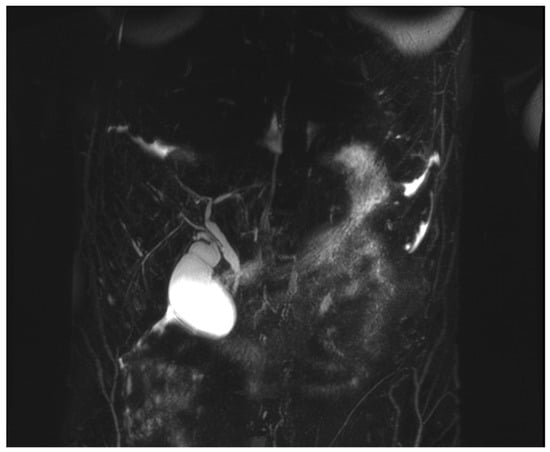

- An MRI with magnetic resonance cholangiopancreatography (MRCP) showed slight beading of the common bile duct, common hepatic duct, and proximal hepatic duct; the common bile duct was dilated to 10 mm in width (see Figure 2).